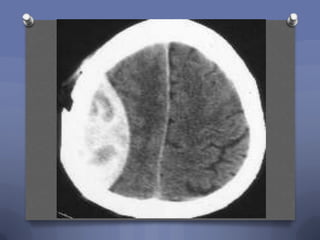

Case 1

O A 2 year-old comes in after falling

approximately 3 feet from her parent‟s bed.

The CT scan shows the following:

What is your diagnosis?

1. Epidural hematoma

2. Subdural hematoma

3. Diffuse axonal injury

4. Contusion

Subdural

Subdural Hematoma

O More common than

epidural in children

O Tears in parasagittal

bridging veins

O Concave shape

O Often associated with

more diffuse shear injury

O Immediate surgical tx if pt

is unconscious and has

subdural bleed

O Suspect NAI